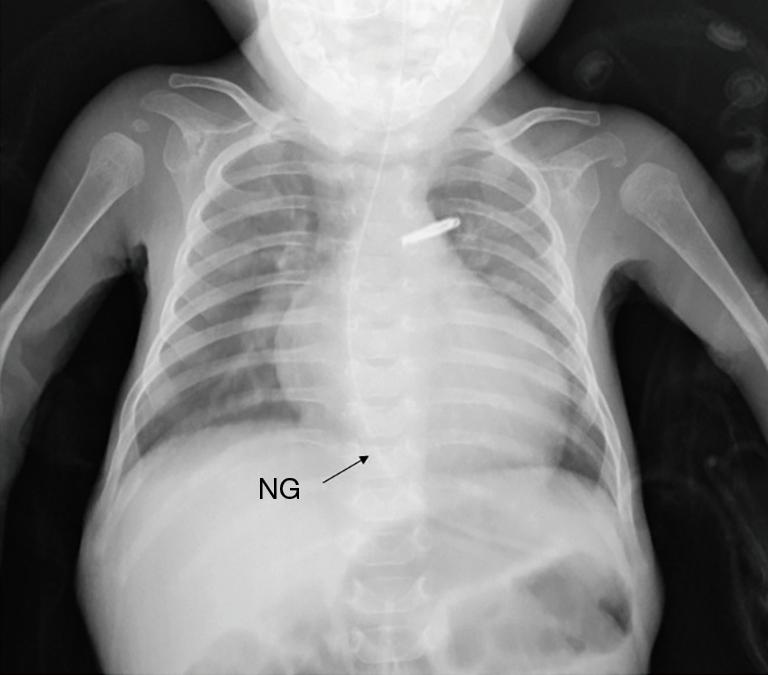

Pulmonary artery banding (PAB) may reduce the need for left ventricular assist devices and heart transplantation in children with end-stage heart failure. However, excessive banding may increase the right ventricular afterload, leading to worsening of heart failure. The estimated right ventricular pressure and the shifting of the interventricular septum by transesophageal echocardiography (TEE), pulmonary artery pressure, right atrial and ventricular pressure, percutaneous oxygen saturation, and mixed venous oxygen saturation are utilized to determine the optimal circumference for PAB. Here, we report the case of a 5-month-old patient with end-stage heart failure due to left ventricular noncompaction cardiomyopathy (LVNC), with a gene mutation of MYH7, who underwent successful PAB. The exact PAB placement was additionally guided by using cerebral regional oxygen saturation (rSO) measurement to achieve a tolerable and optimal PAB effect. We monitored rSO and other hemodynamic parameters while surgeons banded the pulmonary artery to achieve both highest rSO levels and stable hemodynamics. rSO was 68% before banding, and increased and remained at over 90% after the banding at same FiO. Patient's heart failure improved gradually, and the child was discharged home at 6 months after PAB. The rSO is a simple and non-invasive monitor for the measurement of oxygen delivery to the brain tissue. rSO alone would not be able to guide PAB placement in the vulnerable DCM patients, but it may be of one further monitoring value for the optimal pulmonary artery circumference while patients are undergoing PAB.

肺动脉环缩术(PAB)可能会减少终末期心力衰竭儿童对左心室辅助装置和心脏移植的需求。然而,过度环缩可能会增加右心室后负荷,导致心力衰竭恶化。通过经食管超声心动图(TEE)评估右心室压力和室间隔移位、肺动脉压力、右心房和心室压力、经皮血氧饱和度以及混合静脉血氧饱和度,以确定PAB的最佳环缩周长。在此,我们报告一例5个月大的因左心室致密化不全心肌病(LVNC)导致终末期心力衰竭的患者,其存在MYH7基因突变,该患者成功接受了PAB。通过使用脑局部血氧饱和度(rSO)测量来额外指导PAB的精确放置,以实现可耐受且最佳的PAB效果。在外科医生对肺动脉进行环缩时,我们监测rSO和其他血流动力学参数,以实现最高的rSO水平和稳定的血流动力学。环缩前rSO为68%,在相同FiO情况下,环缩后rSO升高并维持在90%以上。患者的心力衰竭逐渐改善,PAB术后6个月患儿出院。rSO是一种用于测量脑组织氧输送的简单且无创的监测方法。单独的rSO无法指导脆弱的扩张型心肌病患者进行PAB放置,但在患者接受PAB时,它可能对确定最佳肺动脉环缩周长具有进一步的监测价值。